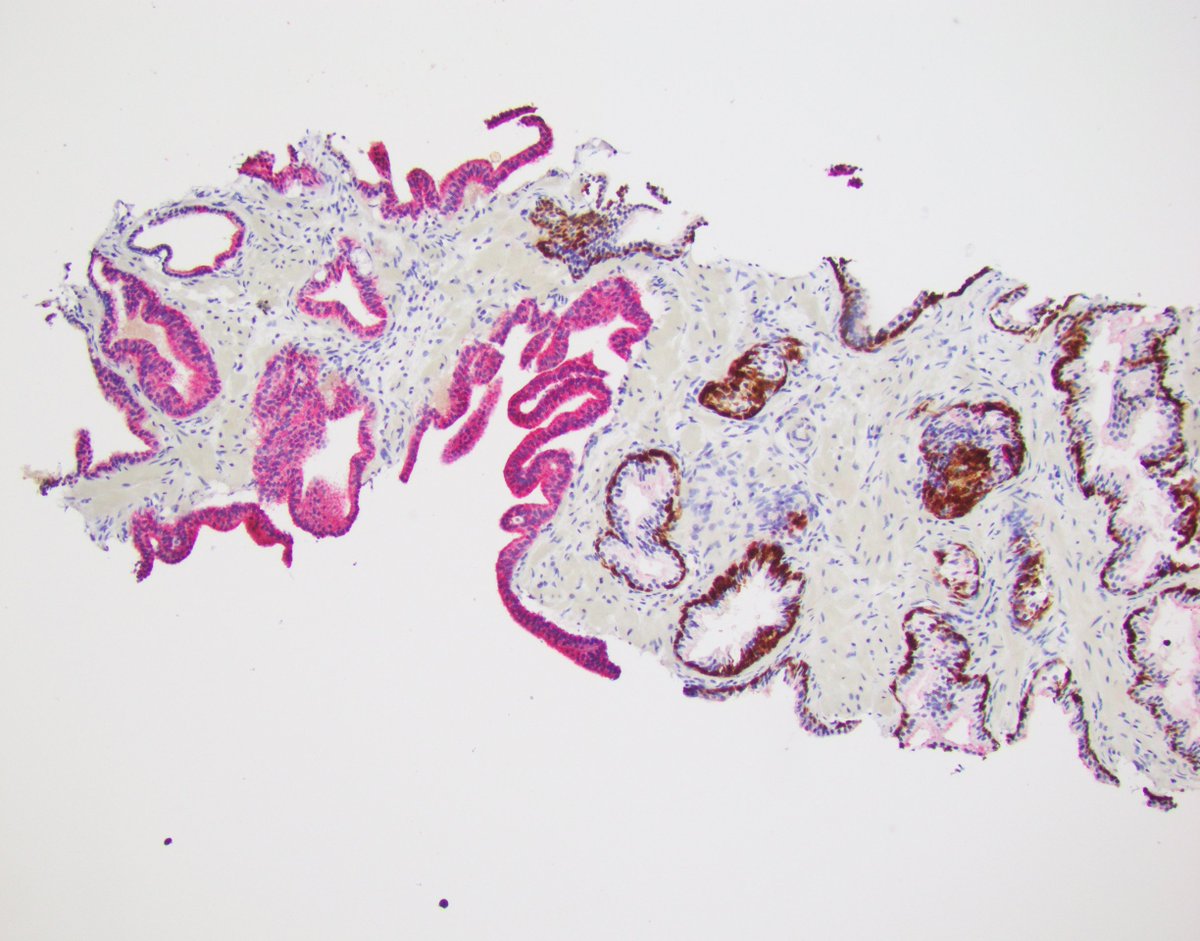

What is your diagnosis? #prostate #gupath #pathology #pathres

Thanks to all who responded! PIN-like PCA 33=6, GG1 🛑⚡️don't brush off as HGPIN-can be tricky on needle biopsies Used to be called HGPIN-like ductal PCA but now re-classified as acinar References: PMID 35758185 & 29297491 #GUPATh #pathology #pathres